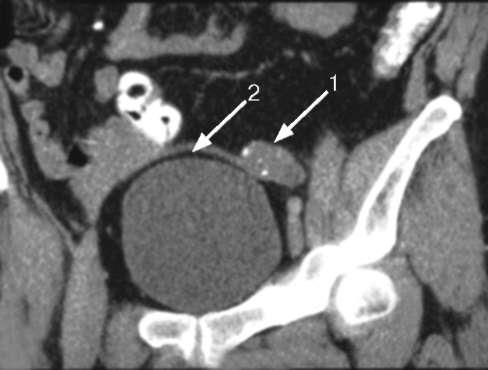

3. МРТ при неопущении яичка:

• Визуализация посредством МРТ должна применяться в УЗ-негативных случаях

• Т1-ВИ: объемное образование овальной формы с низкой интенсивностью сигнала; Т2-ВИ: объемное образование овальной формы с высокой интенсивностью сигнала

- КТ и МРТ органов таза. Компьютерную и магнитно-резонансную томографию применяют при неинформативности ультразвуковых исследований для подтверждения диагноза.

В случаях, когда не удается пропальпировать яичко в паховых каналах, первым этапом назначается УЗИ пахового канала и органов малого таза. При отсутствии яичек в паховых каналах по УЗИ, выполняется диагностическая лапароскопия (уровень доказательности А). Во время диагностической лапароскопии тщательно осматривается малый таз, на предмет возможного дизгенеза гонад, наличия дериватов мюллерого протока. После обнаружения яичек в полости малого таза, оценивается размер яичек, длина сосудов семенного канатика. Если длина сосудов семенного канатика достаточная для низведения, выполняется одномоментная орхипексия по Фаулер-Стефанс. Когда длины сосудов яичка бывает недостаточной для низведения, выполняется первый этап операции Фаулер-Стефанс – пересечение и лигирование тестикулярной артерии, с последующим выполнением второго этапа.